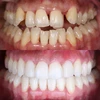

Zirkonyum uygulamalar

Porselen uygulamaları

Laminate veneer